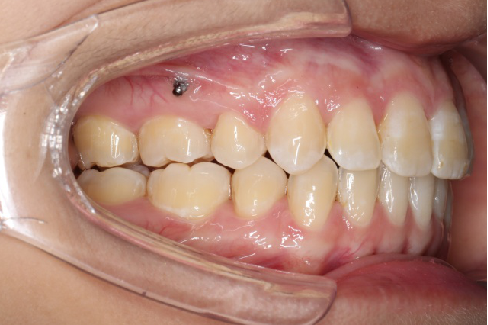

2018.11.14  术后磨牙尖牙I类关系,中线齐,覆合,覆盖正常

Post-TXPRE-TXPost-TXNormFMIA°47°57.555.0SNA°77.7°76.883.0SNB°70.2°73.780.0ANB°7.5°3.13.0FMA° 29.828.026PFH/AFH70.5°65.970Z Angle°50.3°64.477U1-FH113.0103.7110.0 IMPA°103.291.197.0U Lip tos’ line6.3 mm3.25.0L Lip to s’ line3.9 mm1.03.0OP-FH1212.615

宏观评价:面部对称,面下三分一比例协调,上下唇凸度正常,上颌牙列内收转矩控制良好,下颌后缩改善,颏唇沟变得更加柔和,术后达到基本直面型。

迷你观评价:上下牙齿中线与面中线对齐,笑弧协调,微笑时牙龈暴露量正常,微笑时横向正常,左右唇基本对称。

微观评价:牙齿整齐,咬合关系良好,上下前牙转矩及突度控制良好,磨牙关系I类,尖窝咬合关系良好,OB,OJ正常。